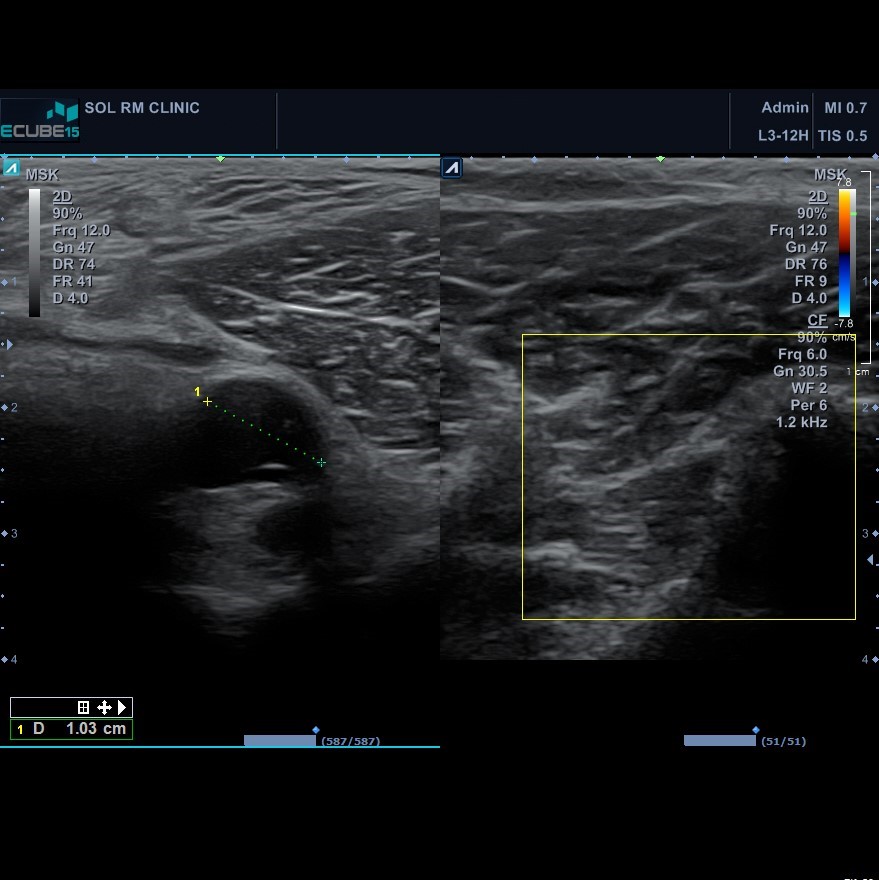

그래서 허리검사를 시행하기보다는 무릎부위 초음파 검사를 시행했습니다. 초음파 검사를 시행하니 오금 외측으로 비골신경 주행 부위까지 확장된 물주머니가 관찰되었고, 이 물주머니가 신경을 누르며 증상을 유발했다고 판단할 수 있었습니다. 이 후 곧바로 주사기로 물주머니에 들어있는 내용물을 흡인하며 10cc정도가 배출되었고, 이 후 곧바로 저림 증상은 사라졌고, 수일 뒤 감각저하 증상도 완전히 호전되었습니다.